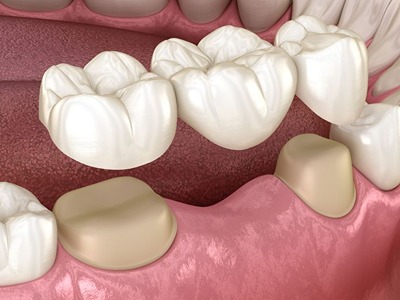

Dr Nitesh Rai, specializes in replacement of teeth with complete dentures, removable partial dentures, fixed partial dentures and Implants.